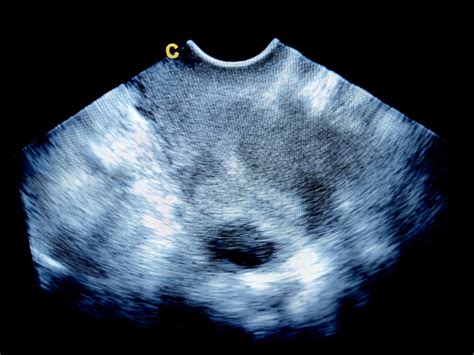

- Ultrazvočni (UZ) pregled: UZ lahko prikaže velikost, obliko in položaj maternice ter izključi prisotnost miomov ali drugih nepravilnosti. Vendar pa, kot je bilo omenjeno, UZ sam po sebi ne pokaže vsega, če zdravnik ni posebej usmerjen na določeno težavo ali če se težava pojavi le ob določenih pogojih (npr. poln mehur).